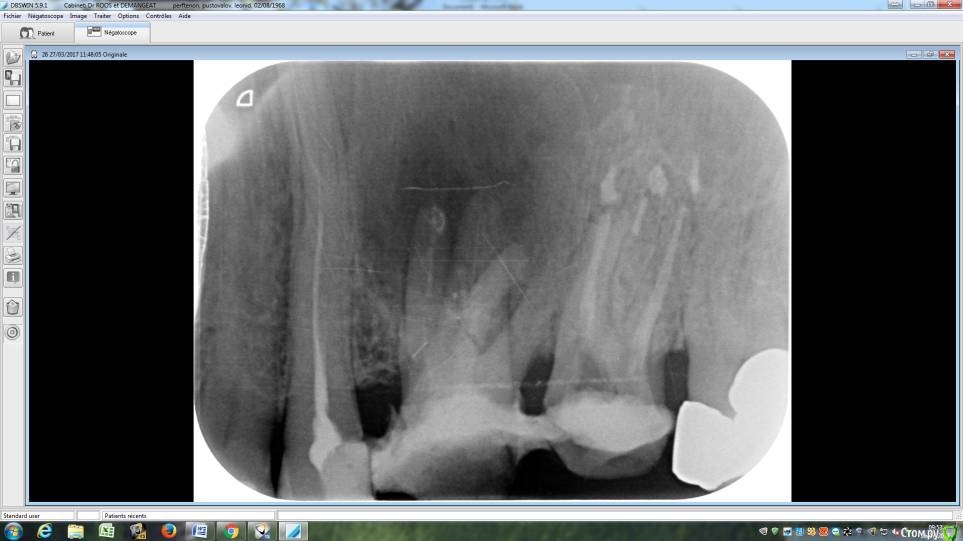

LeoRuss Опубликовано 20 февраля, 2018 Поделиться Опубликовано 20 февраля, 2018 (изменено) Здравствуйте уважаемые метры, в очередной раз обращаюсь к вам за советом.Чуть меньше года назад эндодонтическим методом в полном соответствии с вашими рекомендациями была пролечена киста 26.( http://forum.stom.ru/topic/34508-podsadka-kosti-pri-kiste-nuzhna-li-v-dannom-slucha/ ) При вскрытии зуба выявилась неприятная картина: оба титановых штифта в далеком ‘94м были завернуты мимо корневых каналов прямо в челюсть ;(Док все демонтировал, прочистил под микроскопом и каналы и дыры от штифтов и замуровал МТА : спустя 8 месяцев - 10/2017 : И вроде бы все чудесно, но пару раз за это время десна вокруг зуба воспалялась, и зуб становился более подвижным, но все проходило после 2-3-5 дневного интенсивного полоскания хлоргексидином. Три недели назад была наконец то установлена коронка на соседний 27й, десна с внутренней стороны 26ки тогда была тоже припухшей и протезист посоветовал сходить на контроль к эндодонтисту. Напросился и сходил через неделю, десна за это время еще чуть распухла (только со стороны языка), стало больно при легком нажатии на десну в районе верхушки корня ближнего к 25ке и при покачивании зуба. Док сделал снимок, сказал что все чисто и он понятия не имеет почему все надулось. Вариант удаления забраковал, сказал что по его мнению все хорошо, и можно уже ставить коронку. А вот в импланте смысла никакого, тем более что кости для него пока недостаточно, тк межкорневая область еще не дозаросла. Посоветовал терпеть и.. поставить коронку, тк нагрузка на зуб при жевании должна активировать заживление.Но жевать на этой стороне я стал почти месяц назад, сразу после установки временной коронки на 27, вот с тех пор с 26кой все хуже и хуже. За последние полнедели опухоль сильно увеличилась, и между 25/26, и в сторону нёба, дергает в ритме пульса. Появились отголоски боли в носоглотке и в заглазье.Терпеть уже плохо получается, да и смысла не вижу. Вижу два варианта:1. Удалять 26 чтоб не мучаться, с последующей имплантацией, но как быть с нехваткой кости?2. Вскрыть каналы и прочистить еще раз, но даст ли это хоть что то, да и возможно ли в принципе? В любом случае хотел бы узнать ваше мнение, спасибо ! Изменено 20 февраля, 2018 пользователем LeoRuss Ссылка на комментарий